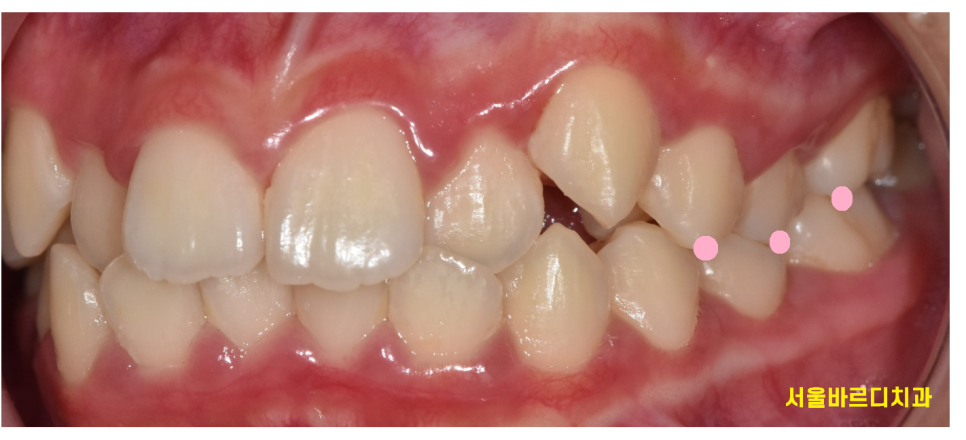

그렇지만 오늘 환자분은 위아래 앞니가 반대로 물리셨는데요!

일반적으로는 윗니가 아랫니를 덮지만

거꾸로 말이죠~~~

이런 교합을 반대교합이라 하는데요

음식을 자르는 기능을 제대로 소화하기 어렵고

치아가 맞닿으면서 깨지거나 손상될 수 있어요.